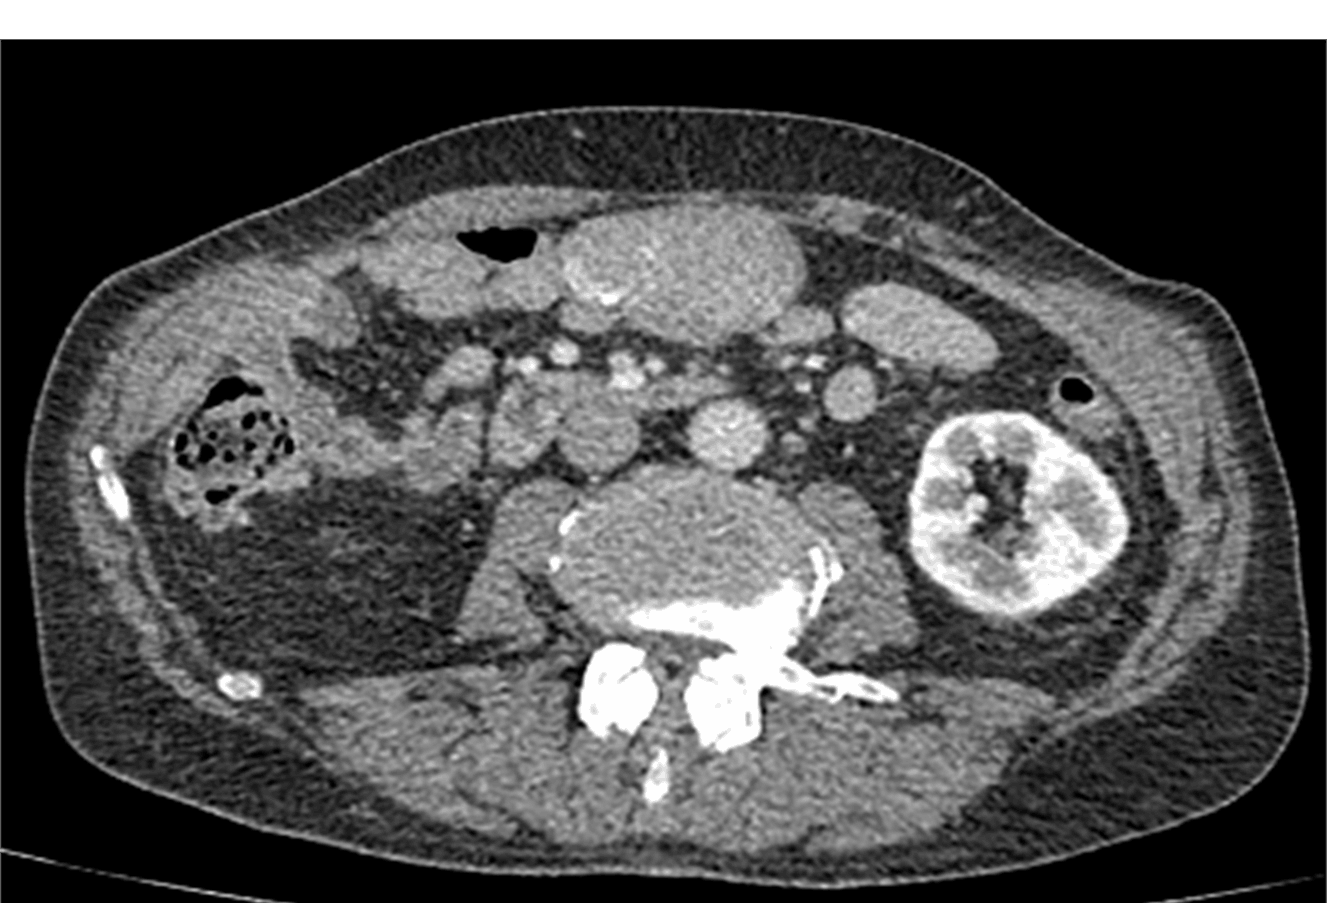

Компьютерная томография.

Позволяет достоверно выявить инородное тело в анатомически сложной области, оценить степень изменений в окружающих тканях, взаимоотношение инородного тела с прилежащими органами, а также выявить наличие возможных осложнений.

Метод выбора для выявления госсипибомы - КТ. В раннем послеоперационном периоде госсипибома наиболее достоверно диагностируется при визуализации округлого образования с губчатой внутренней структурой, с множественными пузырьками газа в структуре. При в/в контрастировании визуализируется тонкое периферическое кольцо контрастного усиления, соответствующее гранулематозному воспалению вокруг инородного тела. В позднем послеоперационном периоде госсипибома может утратить губчатую структуру и КТ-картина может быть сходна с ограниченным скоплением жидкости или с абсцессом. В отдаленном послеоперационном периоде госсипибому следует дифференцировать с новообразованиями, при этом отмечается отсутствие достоверного накопления контрастного вещества как в центральной зоне, так и стенке госсипибомы. В позднем и отдалённом постоперационном периоде также возможна кальцификация стенок госсипибомы.